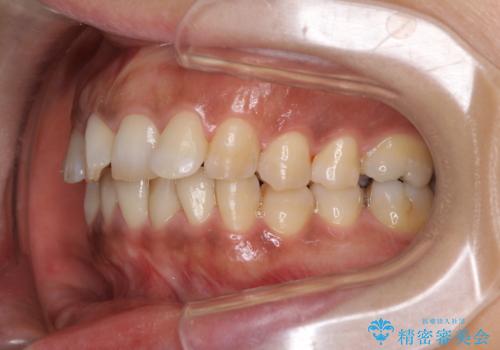

- 上下前歯のデコボコ改善をインビザラインにて行いたいとのことで来院された患者様です。

インビザラインをご希望のことで、IPR(歯と歯の間を削る)などによりスペースを獲得して、排列していくこととしました。

骨格的に上下顎が左右にずれていたため、正中位置は現状を維持したまま歯列不正を解消していくことになります。

なかなか装着時間が守れず、後戻りを繰り返しながら治療を進めたため、インビザライン治療期間期限ギリギリの5年弱の期間を要しました。